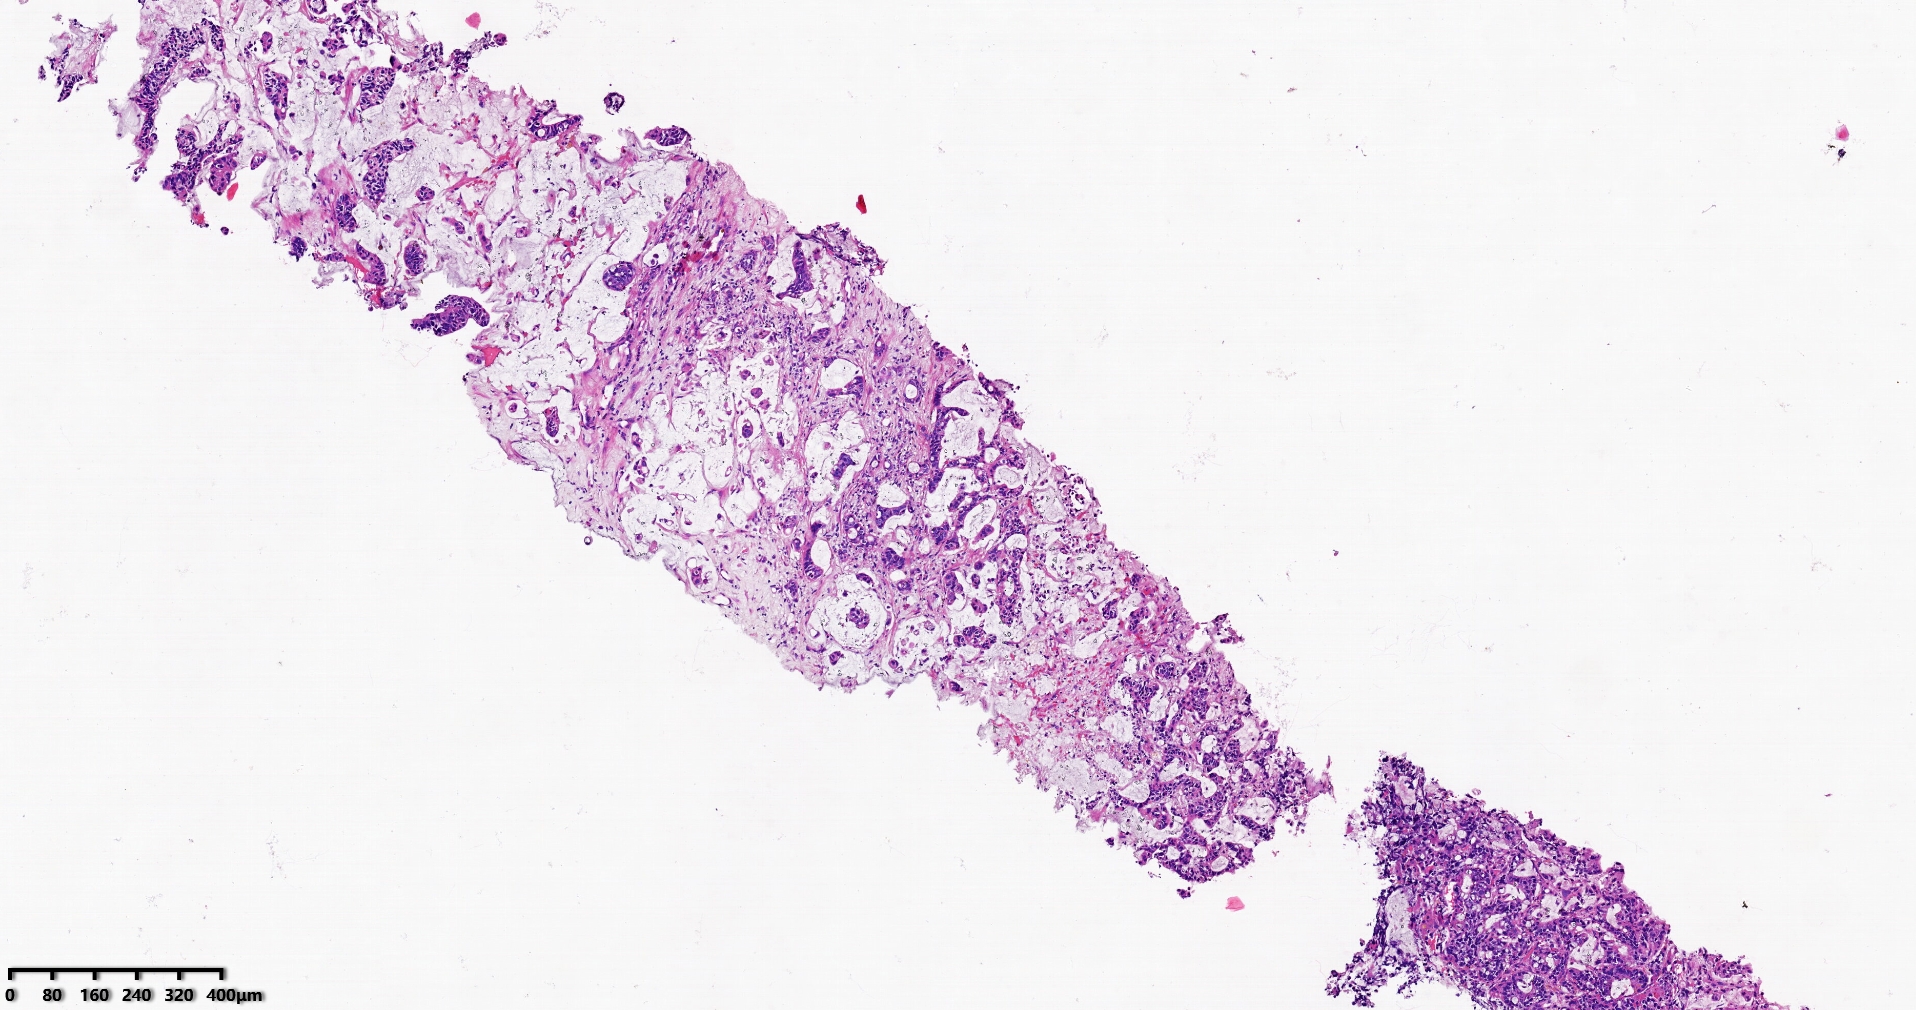

肝穿活检,原发或转移?请路过的老师指导。

标本名称肝脏穿刺

大体所见灰白灰红色穿刺活检组织两条,长1.7-1.9cm,直径0.1-0.2cm。

考虑符合:肝内胆管癌

• rys114:  老师,免疫组化ck7-,ck20+,支持诊断吗?

• whyang315:  当然!

问一问临床其他部位有没有肿瘤病史。

考虑转移性黏液腺癌,消化道来源可能,建议做免疫组化,排除胆管源性。